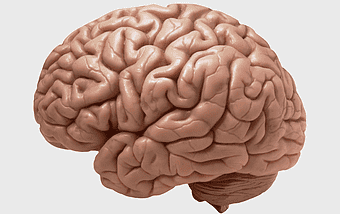

3D brain model, human brain anatomy, neuroplasticity research, brain lateralization, cerebral cortex structure, neural pathways visualization, brain function imaging -